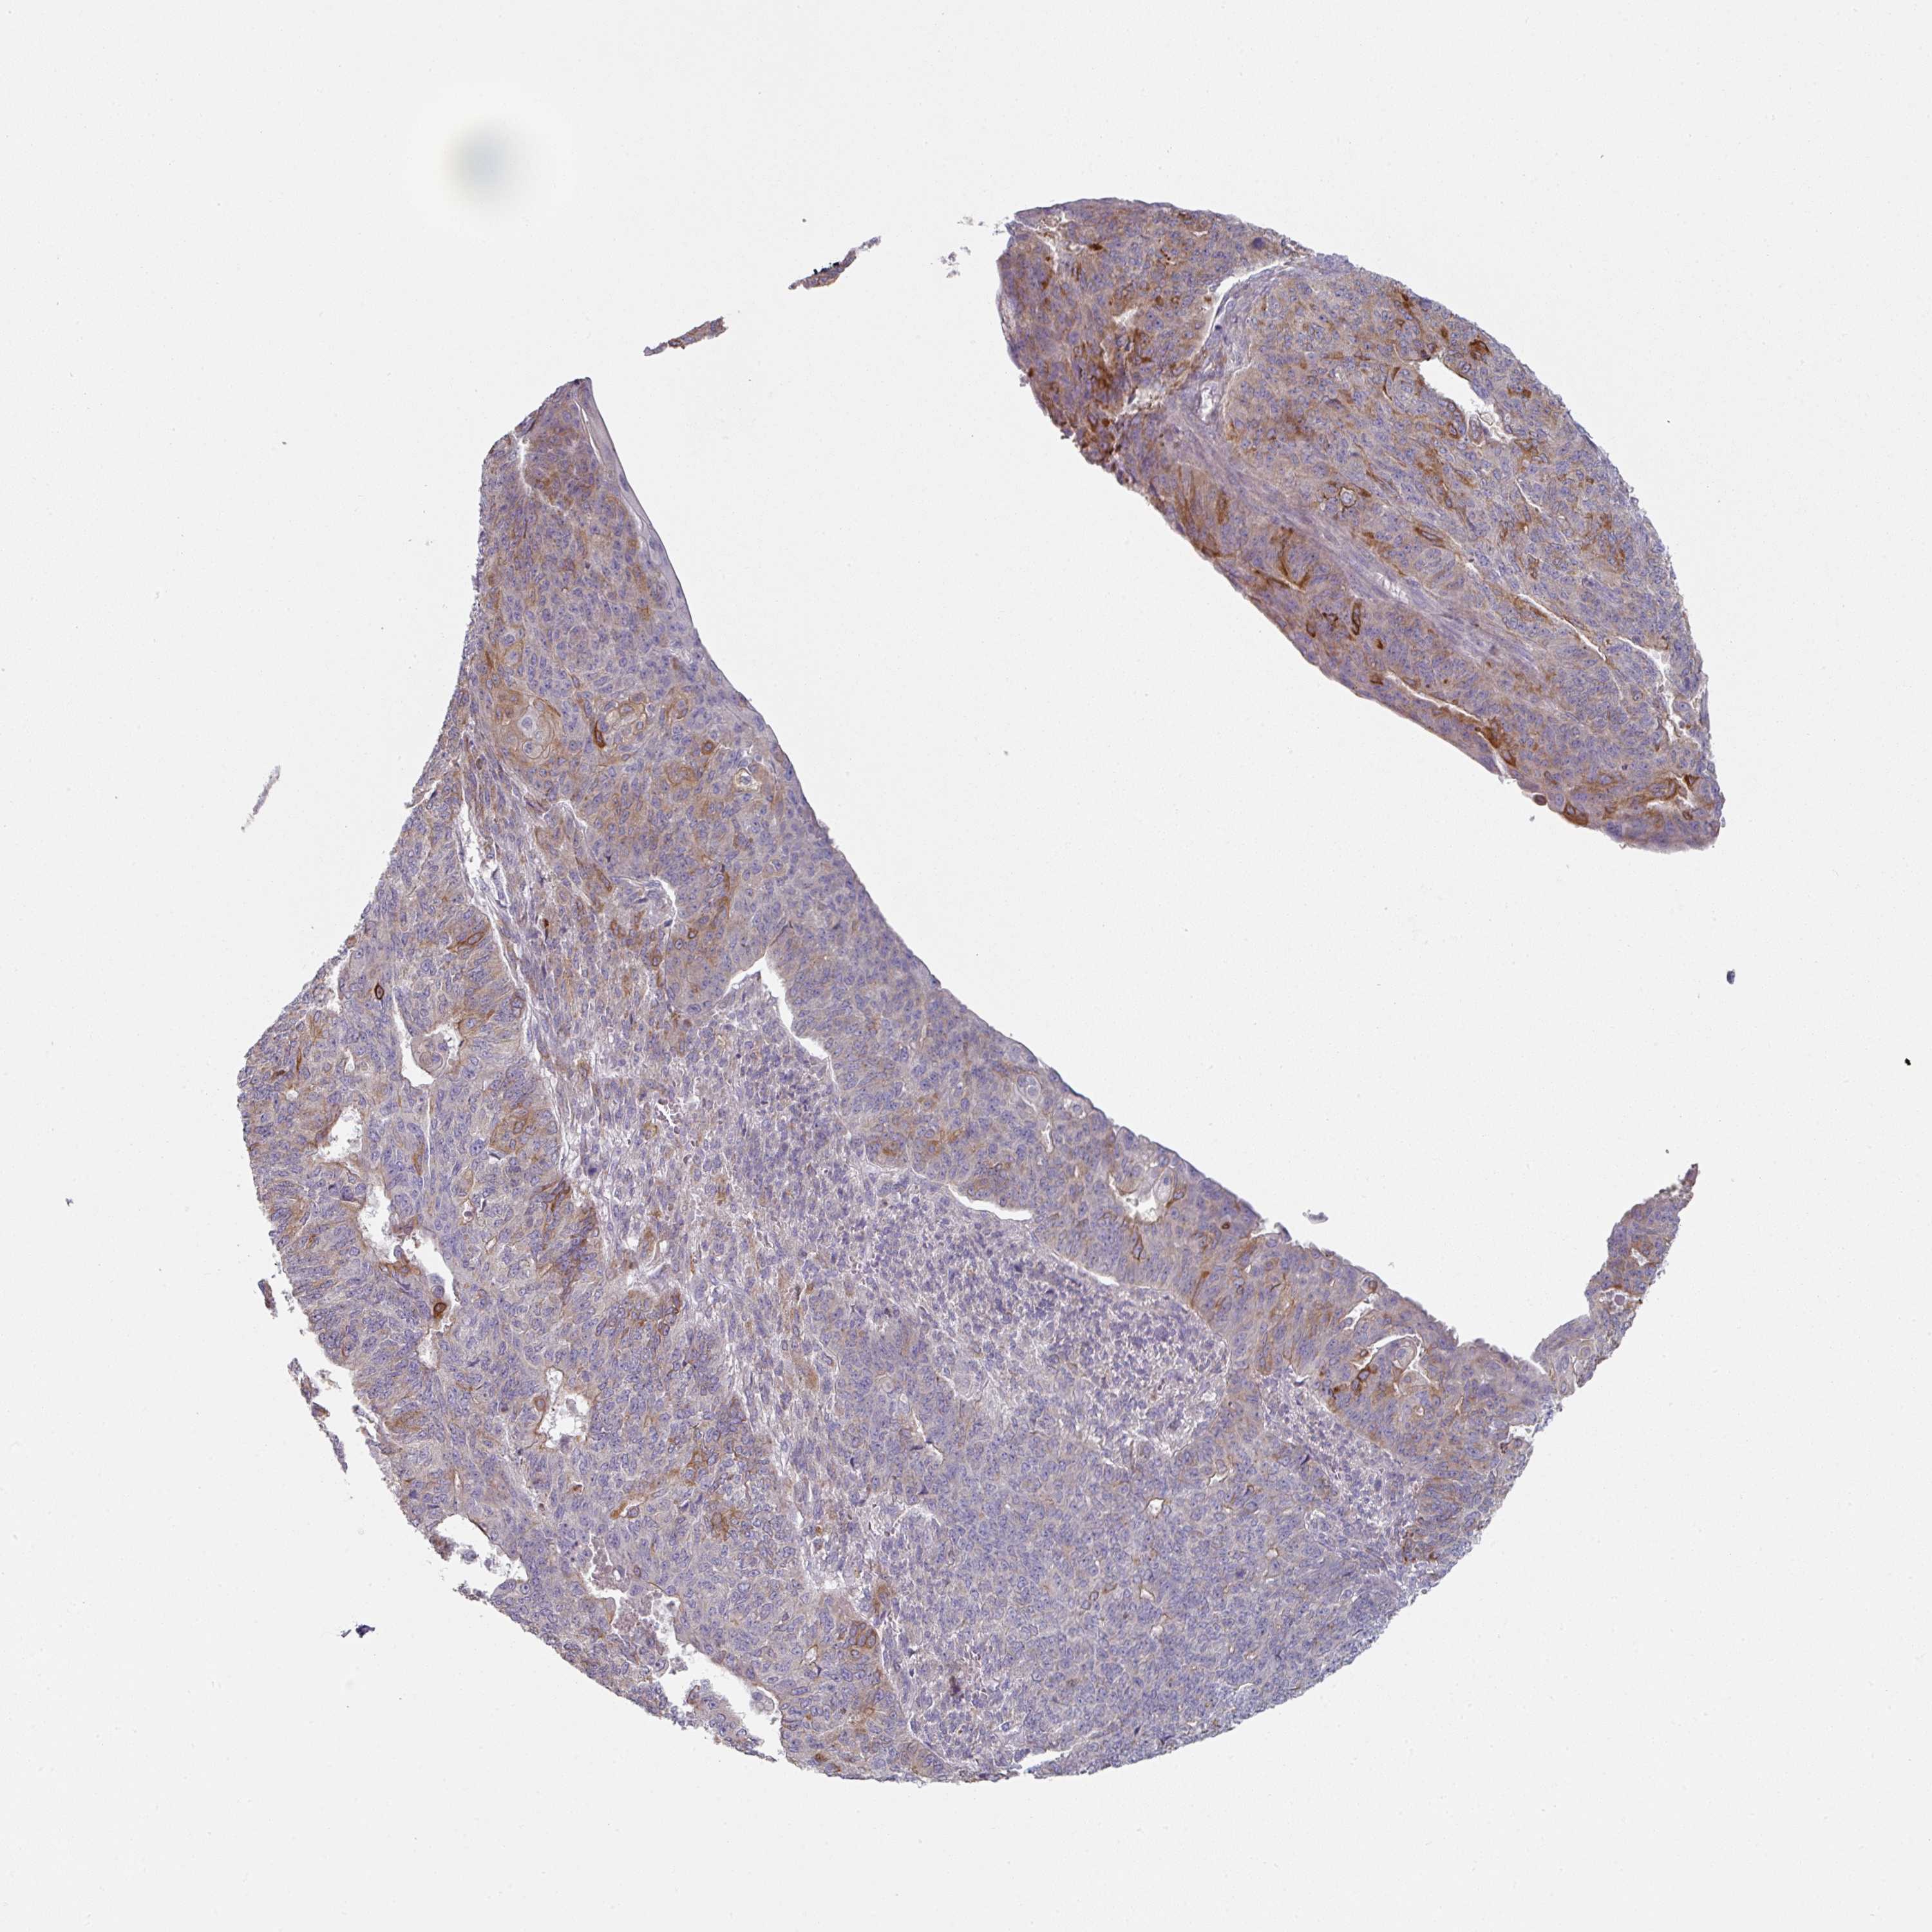

ENDOMETRIAL CANCER - Protein expressioni

A mouse-over function shows sample information and annotation data. Click on an image to view it in a full screen mode. Samples can be filtered based on level of antibody staining by selecting one or several of the following categories: high, medium, low and not detected. The assay and annotation is described here.

Note that samples used for immunohistochemistry by the Human Protein Atlas do not correspond to samples in the TCGA dataset.

Antibody stainingi

Antibody staining in the annotated cell types in the current human tissue is reported as not detected, low, medium, or high, based on conventional immunohistochemistry profiling in selected tissues. This score is based on the combination of the staining intensity and fraction of stained cells.

Each image is clickable and will lead to virtual microscopy that enables deeper exploration of all samples and also displays staining intensity scores, fraction scores and subcellular localization as well as patient and tissue information for each sample.

Antibody HPA052606

Antibody HPA077139

Staining

High

Medium

Low

Not detected

Intensity

Strong

Moderate

Weak

Negative

Quantity

>75%

75%-25%

<25%

None

Location

Nuclear

Cytoplasmic/membranous

Cytoplasmic/membranous,nuclear

Adenocarcinoma, NOS